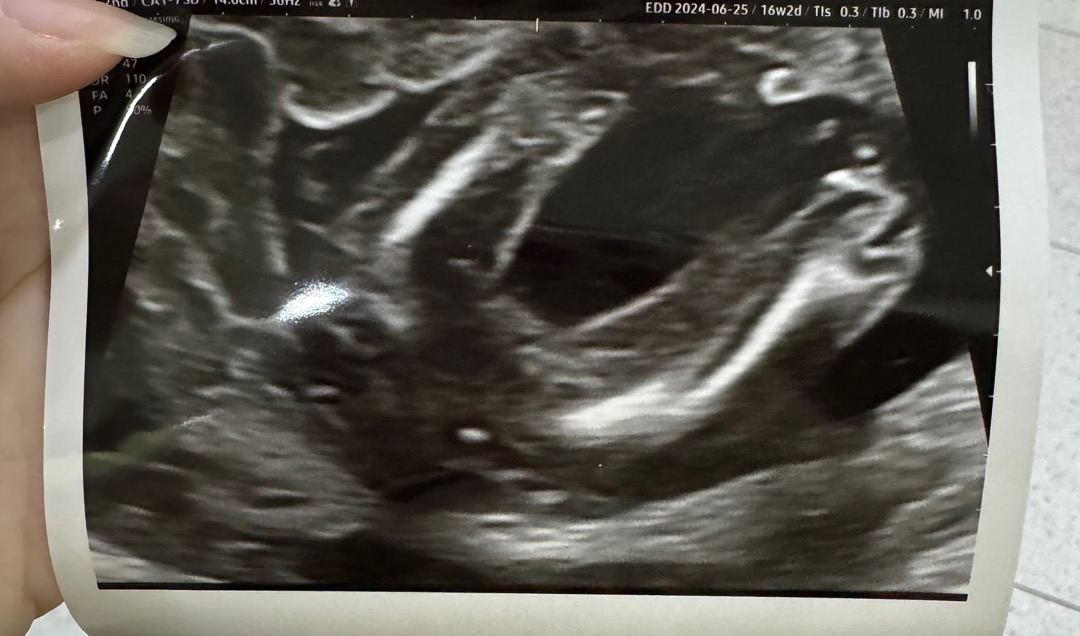

16주 2일차임니다 ㅎㅎ 공주를 원하긴 했지만 .. 진짜 아무 꼬깔콘이나 흔적 없이 깔~~~~꿈한데 이정도면 반전 없이 공주님 99.99999% 확정 맞겠죠? 자꾸 쌤이 혹시모룬다고 반전 있을 수 있다고 겁주시는데 .. 한달 후 진료때까지 기다리라는데 .... 언능 쇼핑하고 싶어요 헤헤 🩷

딸은 진짜 혹시나 마지막까지도 반전은 있더라구요 ㅋ 20주까지는 그래도 기다려 보시는게

공주 맞아요~ 저희 첫째 촘파랑 똑같네요^^